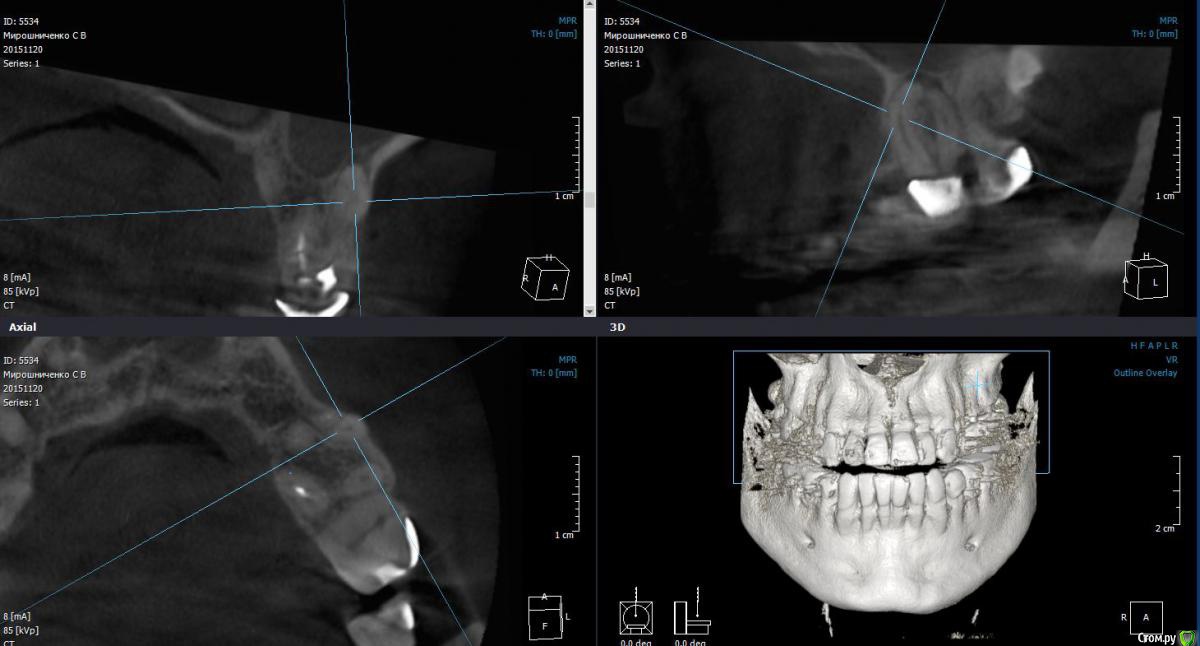

St. Опубликовано 23 марта, 2016 Автор Поделиться Опубликовано 23 марта, 2016 Совсем фейл. Повторное эндо. Сломала на финише профайл 30,04. Вроде обошла 15, но ротари ушла в сторону. Пац обо всем предупрежден. Наблюдаем. Решили не доставать ибо по твердым тканям там и так печаль, если спрямить доступ большая вероятность ленточной перфы. А что бы в таком случае сделали вы? 3 Ссылка на комментарий